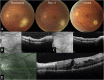

Observations: This single site, retrospective case series reviewed 4 patients with primary ocular toxoplasmosis that was acquired by ingesting undercooked venison. De-identified data was collected regarding baseline patient characteristics including age, sex, past medical and ocular history, onset of symptoms, visual acuity (VA), response to treatment, and workup. All patients with acquired toxoplasmosis had similar chronology of systemic and ocular symptoms. Exposure occurred in October or November and systemic symptoms developed within 2 weeks, followed by ocular symptoms an average of 2.6 months later. Average age at onset was 56 ± 13 (age ± SD) years old and all were male. Average initial and final VA were 20/50 and 20/50, respectively. Positive anti-toxoplasma IgM and IgG serologies were found in all cases. All patients were treated with trimethoprim/sulfamethoxazole and achieved rapid improvement. Complications occurred in 50% of cases and included epiretinal membrane, cystoid macular edema, vitreoretinal traction, and neovascularization.

Conclusions and importance: Consumption of undercooked venison is a source of primary ocular toxoplasmosis even in immunocompetent hosts and has a clear chronology. A presentation of retinochoroiditis during the winter months should prompt questioning for exposure to wild game.